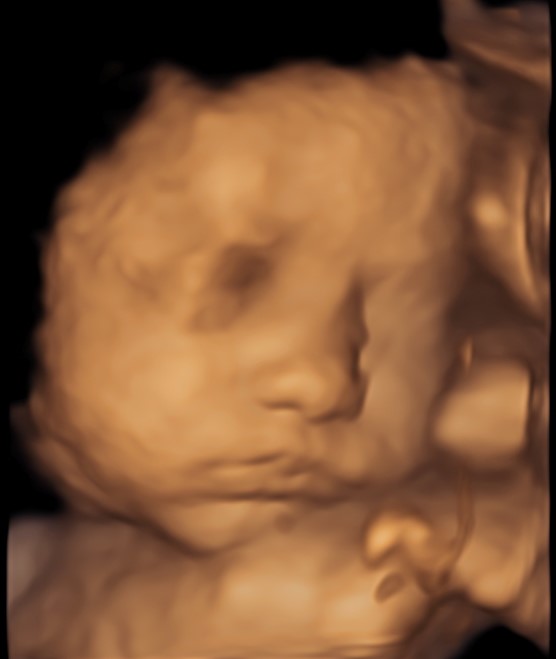

Monmouth County’s First 4D/5D/HD Live Ultrasound Studio

4D/5D/HD Ultrasound Gallery

Gallery